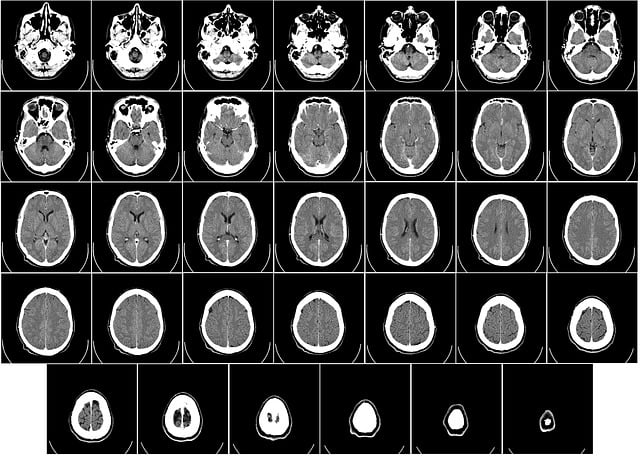

뇌수막종은 뇌를 감싸고 있는 막, 즉 수막에서 발생하는 종양을 의미합니다. 대부분은 양성이지만, 위치와 크기에 따라 다양한 신경학적 증상을 유발할 수 있기 때문에 조기 발견이 중요합니다. 폐경기 증상과 비슷한 양상의 증상을 보이는 경우가 있어 진단이 늦어질 수 있습니다. 뇌수막종의 주요 증상은 두통, 어지럼증, 시야 흐림, 청력 저하, 기억력 감퇴, 성격 변화, 경련 등입니다. 이 중에서도 두통과 어지럼증, 집중력 저하는 폐경기 증상과 매우 흡사하게 나타나 혼동을 일으킬 수 있습니다. 그러나 뇌수막종의 경우 이러한 증상이 점진적으로 악화되거나 지속적이고 한쪽 신체에 국한된 증상이 나타날 수 있어 폐경기와는 구별되는 부분입니다. 뇌수막종의 원인은 아직 명확하게 밝혀지지는 않았지만, 방사선 노출, 유전적 요인, 여성 호르몬과의 연관성 등이 제기되고 있습니다. 실제로 여성에게 더 자주 발생하는 것으로 알려져 있으며, 폐경기 전후 여성에게 진단되는 사례가 증가하고 있는 추세입니다. 이는 뇌수막종 세포가 에스트로겐이나 프로게스테론 수용체에 반응하기 때문으로 해석되고 있습니다. 이 종양은 성장 속도가 느린 경우가 많아 초기에 발견되기 어렵고, 무증상으로 오랜 기간 동안 존재할 수 있습니다. 하지만 종양이 크기를 키우게 되면 뇌압 상승, 신경 압박 등으로 인해 증상이 분명해지기 시작합니다. 두통이 계속되고 진통제로도 완화되지 않거나, 일상적인 기억력이 심하게 떨어지고, 행동이 변하는 등의 이상 증상이 지속된다면 조속한 검사가 필요합니다. 진단은 MRI, CT 등 영상 검사로 가능하며, 종양의 위치와 크기에 따라 치료 방법이 결정됩니다. 수술적 제거가 일반적이나, 고령이거나 위험한 위치일 경우 감시 또는 방사선 치료가 병행되기도 합니다. 최근에는 감마나이프 등의 정밀 방사선 기술로 비침습적 치료도 가능해졌습니다. 건강검진 시 뇌 MRI를 정기적으로 받는 것이 예방 차원에서 도움이 되며, 가족력이나 반복적인 신경학적 증상이 있는 경우에는 보다 면밀한 관찰이 필요합니다.